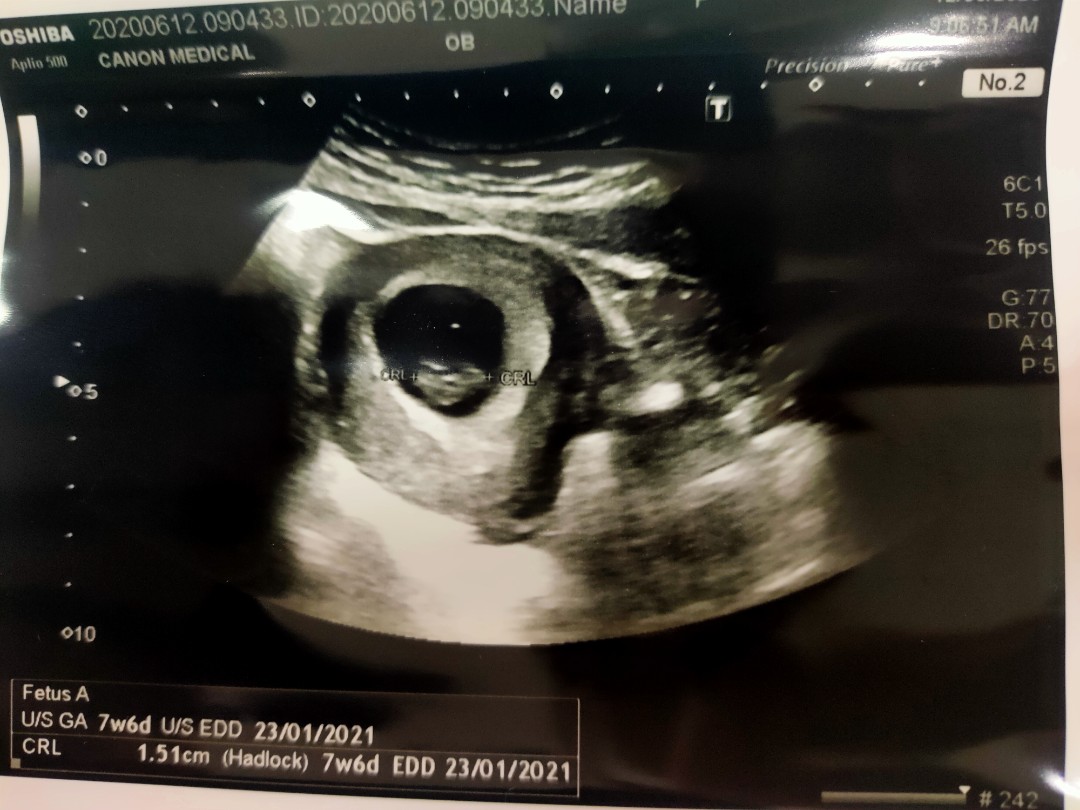

8weeks 4day

hye,so this morning i went to clinic for a scan. But doctor said she only see the sac. There is no baby. She suggested to wait for two weeks before i scan again. Is it normal? sorry for bad english

Baca lagisama sya pun mcm tu xnampak bila scan dah 2kali mungkin masih kecik doktor cakap. suruh datang 2week lagi scan. saya scan kat swasta kandungan dah 8week. doktor fikir saya x pragnant 🤣 guna 5x test positif tu yg suruh dtg lagi. dah muntah2 nafsu makan ada lapar je tapi tu la asik muntah. boleh pulak x pragnant

baby berapa cm masatu... sy td g kk cek juga.. tarikh lahir lain plak.. die. suh dtglagi 2mgu